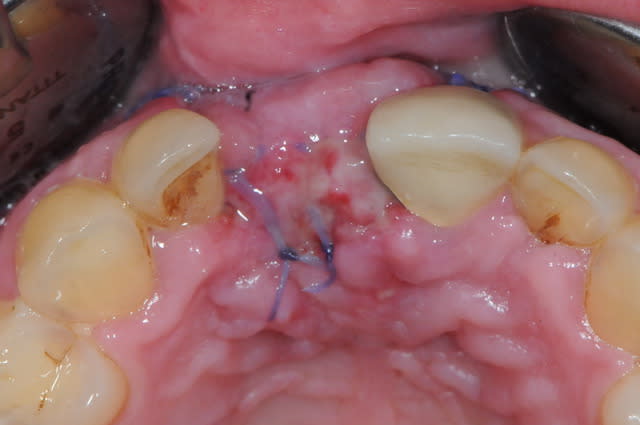

pourquoi utilises tu encore cette merde de vicryl, tu gagnerais beaucoup à passer au PTFE.

Dommage que tu n'aies pas décalé tes incisions de décharges, ça t'aurait évité d'avoir une récession gingivale post operatoire sur 21 !

oui, très juste, c'était une grooossssse connerie de ma part. je sais pas ce qui m'a pris, je comprends pas!

pas du vycril, du PGA de chez stoma ! oups, c'est pareil ! :)

tu utilises quoi comme fil? la marque ?